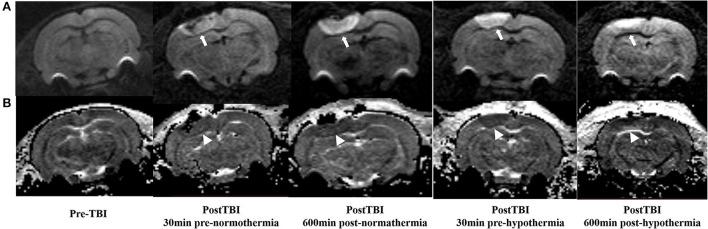

The glymphatic system has recently been shown to clear brain extracellular solutes and can be extensively impaired after traumatic brain injury (TBI). Despite hypothermia being identified as a protective method for the injured brain via minimizing the formation of edema in the animal study, little is known about how hypothermia affects the glymphatic system following TBI. We use dynamic contrast-enhanced MRI (DCE-MRI) following cisterna magna infusion with a low molecular weight contrast agent to track glymphatic transport in male Sprague-Dawley rats following TBI with hypothermia treatment and use diffusion-weighted imaging (DWI) sequence to identify edema after TBI, and further distinguish between vasogenic and cytotoxic edema. We found that hypothermia could attenuate brain edema, as demonstrated by smaller injured lesions and less vasogenic edema in most brain subregions. However, in contrast to reducing cerebral edema, hypothermia exacerbated the reduction of efficiency of glymphatic transportation after TBI. This deterioration of glymphatic drainage was present brain-wide and showed hemispherical asymmetry and regional heterogeneity across the brain, associated with vasogenic edema. Moreover, our data show that glymphatic transport reduction and vasogenic edema are closely related to reducing perivascular aquaporin-4 (AQP) expression. The suppression of glymphatic transportation might eliminate the benefits of brain edema reduction induced by hypothermia and provide an alternative pathophysiological factor indicating injury to the brain after TBI. Thus, this study poses a novel emphasis on the potential role of hypothermia in managing severe TBI.

最近研究表明,类淋巴系统可清除脑内细胞外溶质,且在创伤性脑损伤(TBI)后会受到广泛损害。尽管在动物研究中,低温被确定为一种通过减少水肿形成来保护受损大脑的方法,但关于低温如何影响TBI后的类淋巴系统,人们知之甚少。我们在雄性Sprague-Dawley大鼠TBI并接受低温治疗后,通过在小脑延髓池注入低分子量造影剂后进行动态对比增强磁共振成像(DCE-MRI)来追踪类淋巴转运,并使用扩散加权成像(DWI)序列来识别TBI后的水肿,并进一步区分血管源性水肿和细胞毒性水肿。我们发现,低温可减轻脑水肿,大多数脑区的损伤灶较小且血管源性水肿较少即证明了这一点。然而,与减轻脑水肿相反,低温加剧了TBI后类淋巴转运效率的降低。这种类淋巴引流的恶化在全脑均存在,并表现出半球不对称性和全脑区域异质性,与血管源性水肿相关。此外,我们的数据表明,类淋巴转运减少和血管源性水肿与血管周围水通道蛋白-4(AQP)表达降低密切相关。类淋巴转运的抑制可能会消除低温诱导的减轻脑水肿的益处,并提供一个表明TBI后脑损伤的替代病理生理因素。因此,本研究对低温在严重TBI治疗中的潜在作用提出了新的强调。